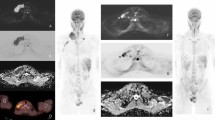

The sensitivity and specificity of combining short-axis-diameter ≥10-mm size threshold applied to all nodes, followed by ADC cut-off values of 0.77, 1.15 and 1.79×10−3 mm2 s−1 to 5- to 9-mm lymph nodes for both readers, are given in Table 4. Figures 7 and 8 demonstrate examples of true-positive and false-positive whole-body MRI nodal classification using the combined short-axis diameter and ADC threshold.

Images in a 15-year-old boy with Hodgkin lymphoma. a Axial 18flourine-2-fluoro-2-deoxyglucose (FDG) positron emission tomography (PET)/CT shows a positive left axillary node (arrow). b Axial short tau inversion recovery half-Fourier acquisition single-shot turbo-spin-echo (repetition time/echo time [TR/TE] = 800/60 ms) MR image demonstrates an 8-mm short-axis-diameter left axillary node (arrow). c Axial diffusion-weighted imaging (DWI; b=500 s/mm2; TR/TE=4,900/66 ms) demonstrates an 8-mm short-axis-diameter left axillary node. These findings would result in false-negative nodal classification according to the threshold of short-axis diameter ≥10 mm. d Apparent diffusion coefficient (ADC) map demonstrates the same left axillary node (arrow) with an ADC of 0.8×10−3 mm2 s−1. The node was deemed positive on whole-body MRI using the combined short-axis diameter ≥10 mm and ADC cut-off of <1.15×10−3 mm2 s−1 classification — a true-positive result compared with using the FDG PET/CT reference

Images in a 16-year-old girl with Hodgkin lymphoma. a18Flourine-2-fluoro-2-deoxyglucose (FDG) positron emission tomography (PET)/CT is deemed negative for left cervical nodal involvement. b Axial short tau inversion recovery half-Fourier-acquisition single-shot turbo-spin-echo (repetition time/echo time [TR/TE] = 800/60 ms) MR image demonstrates a 5-mm short-axis-diameter left cervical node (arrow). c Axial diffusion-weighted imaging (DWI; b=500 s/mm2; TR/TE=4,900/66 ms) demonstrates a 5-mm short-axis-diameter left cervical node (arrow). These findings would result in true-negative nodal classification. d Apparent diffusion coefficient (ADC) map demonstrates the same left cervical node (arrow) with ADC of 0.9×10−3 mm2 s−1. The node was deemed positive on whole-body MRI by combined short-axis diameter ≥10 mm and ADC cut-off value of <1.15×10−3 mm2 s−1 classification — a false-positive result compared with using the FDG PET/CT reference